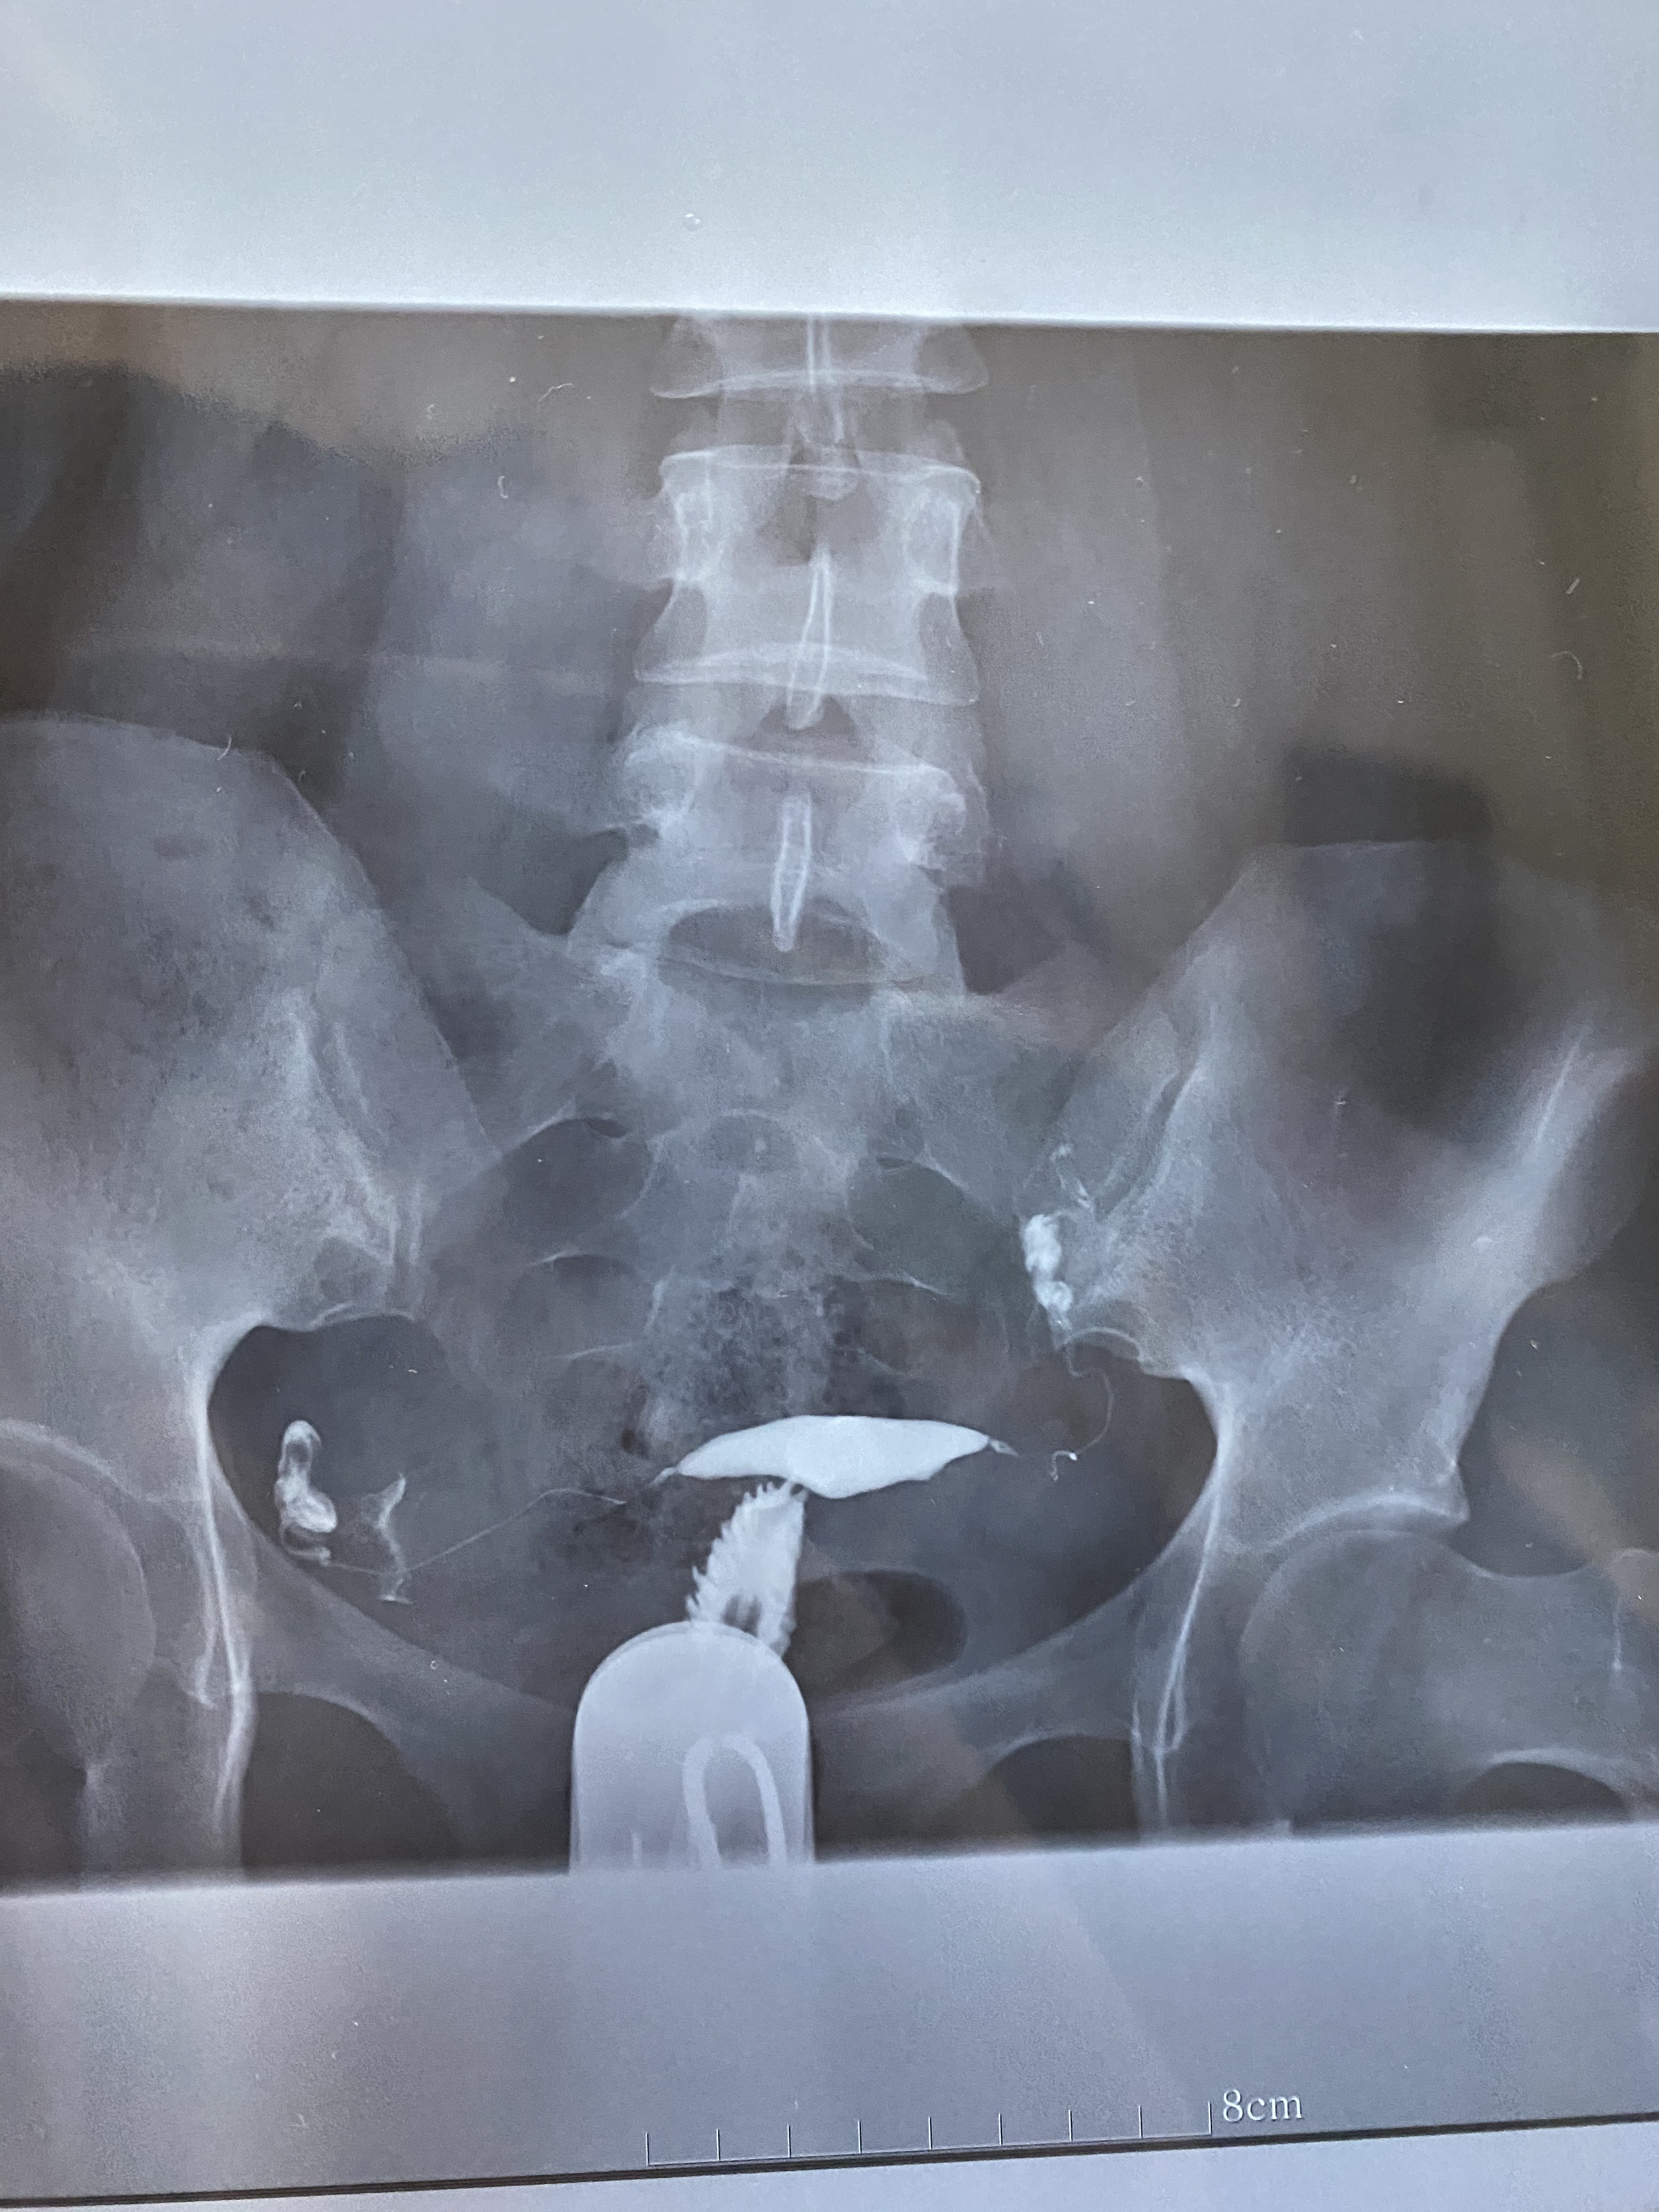

医生您好,帮我看看输卵管报告,报告上虽然没有异常,但片子看着左侧有点上举,这样影响怀孕吗?另外我b超显示宫腔中段有子宫内膜息肉0.5×0.3备孕快一年了没怀孕,我不孕的原因是因为息肉还是也和输卵管有点关系?

上举点不影响怀孕的,内膜息肉不大,但一年不怀孕,应该把息肉切除,有的切除息肉就可以怀孕的,同时男方查精液常规。